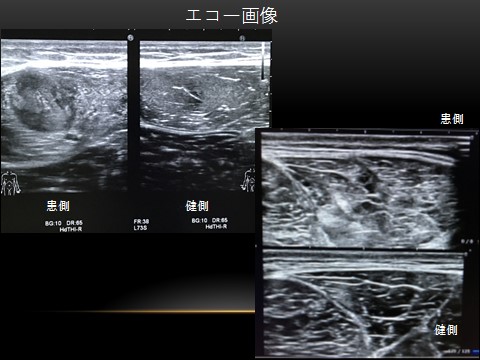

肉離れのエコー画像

当院では身体所見・エコー・MRIなどを用いて多角的に評価することで正確な診断を心掛けています。分類にはJISS分類(国立スポーツ科学センター奥脇先生考案)を用い、初診時にある程度の復帰時期までの治療計画設定を行います。

やみくもに安静とすることなく、早期から患部トレーニングを開始できるように専門のリハビリテーションスタッフと連携をとっています。